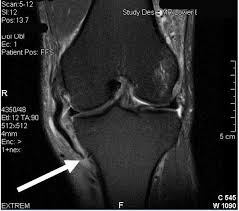

Your activity level before the injury, your weight and other factors all need to be considered before your doctor can estimate how long your grade 2 knee sprain recovery will take. Grade l (minimal) mild pain, localized swelling, tenderness, stability. When this happens, you face a recovery time of weeks to months, depending on the grade of the mcl tear. This is a mild sprain that damages the ligament but does not cause significant tearing. Grade 2 usually means partial tearing of the ligaments in the ankle. Grade 2 ankle sprains occur when the ligaments in the ankle become stretched or torn. Rehabilitation exercises will be the same as for a grade 2 injury once the ligament has healed. If correctly immobilised, a compete ligament tear can heal without the need for surgery. What is the recovery time for a medial collateral ligament or mcl tear? The knee joint has lost functionality. For a grade ii injury, it may take six weeks to heal; For a grade i injury, it may take a few weeks to heal; Significant tenderness and swelling around the ankle

The knee joint has lost functionality. The typical recovery time for a grade 2 sprain is approximately two to four weeks, per jung, though of course every situation varies. But ligament sprain may take from month to year for full recovery. Significant tenderness and swelling around the ankle Grade 2 sprained ankles often involve a partial tear in ligaments. Some patients may need to wear a fracture walker for about three to 12 weeks. A sprain is usually caused by the joint being forced suddenly outside its usual range of movement and the inelastic fibres are stretched. If the doctor moves the ankle in certain ways, there is an abnormal looseness of the ankle joint; The surgery is called a knee ligament repair and it involves stitching the torn ligament. To correctly estimate the time of recovery you first have to classify or grade the mcl tear. Treatment of an mcl tear depends on the severity of the injury. It may take several months before a. A grade 2 sprained ankle should not be treated at home unless you or someone who can care for you is a medical professional.